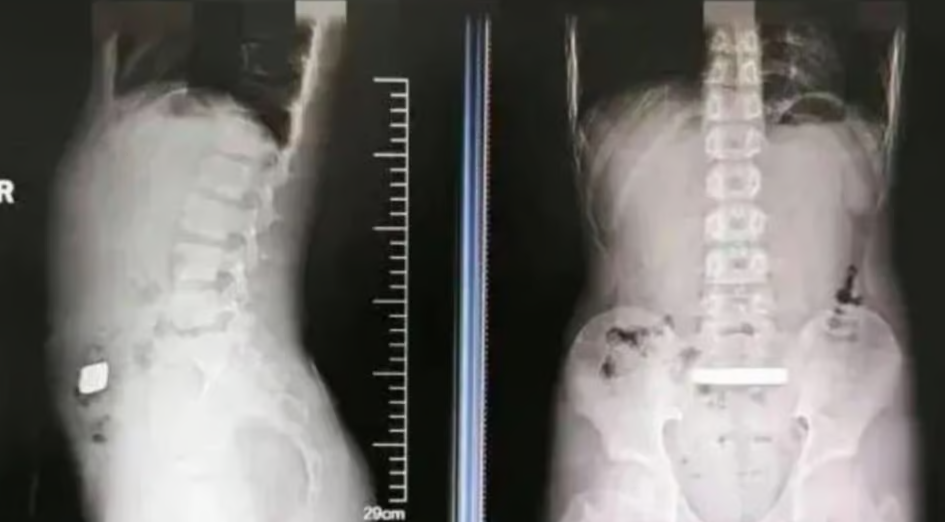

В одной из детских больниц Китая медики провели крайне необычную операцию, где 11-летнему мальчику, по имени Цянь, удалили из желудка настоящий золотой слиток весом 100 граммов. Врачи были удивлены, когда увидели на рентгеновском снимке драгоценный металл внутри парня.

Родители парня рассказали, что он находился в своей комнате, где внезапно пожаловался на боль в животе. Подозревая что-то серьезное, его родители обратились в детскую больницу. После обследования и рентгена врачи заметили неожиданный металлический предмет – слиток золота.

Медики поначалу пытались обойтись без хирургического вмешательства. Парню назначили слабительные средства, надеясь, что слиток пройдет естественным путем. Но после двух суток никаких изменений не произошло. Драгоценный металл оставался в том же месте и создавал риск осложнений кишечной непроходимости.

Рентгеновский снимок обнаружил слиток золота. Фото: Douyin